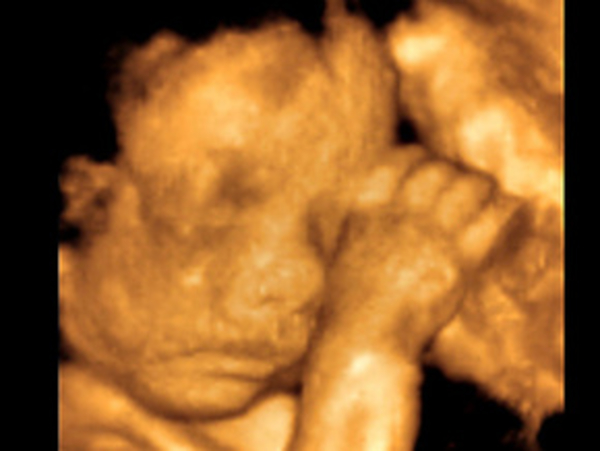

Самое поразительное, что не рожденный ребенок, находящийся в чреве матери, уже обладает чувством прикосновения, слышит, реагирует на боль, давление, громкие звуки, сосет и глотает, даже улыбается!

Исследования показали, что к двадцать пятой неделе эмбрион уже может двигать руками и туловищем, выражая свои удовольствия и неудовольствия кивками и гримасами. К четвертому месяцу у него уже развивается мимика: он может улыбаться, хмуриться. Еще через несколько недель он уже реагирует на любое прикосновение: вот почему так важно матери и близким гладить живот, чтобы ребенок воспринимал ласку.